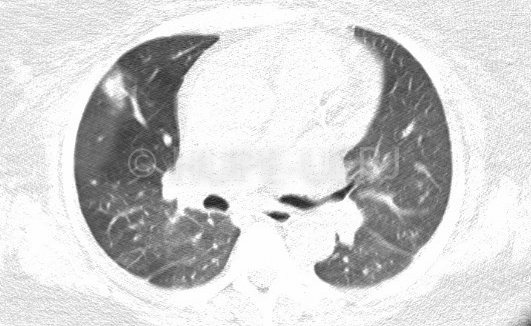

Doente jovem com diagnóstico de linfoma, duas tomografias de tórax, a segunda realizada um mês após, com piora nítida (nódulos e massas pulmonares, massa axilar esquerda). Evolução arrastada de espondilodiscite (destruição de vários corpos contíguos e coleção que se dissemina para região paravertebral e iliopsoas). Diversas lesões ósseas no ilíaco.

Evolução após um mês: